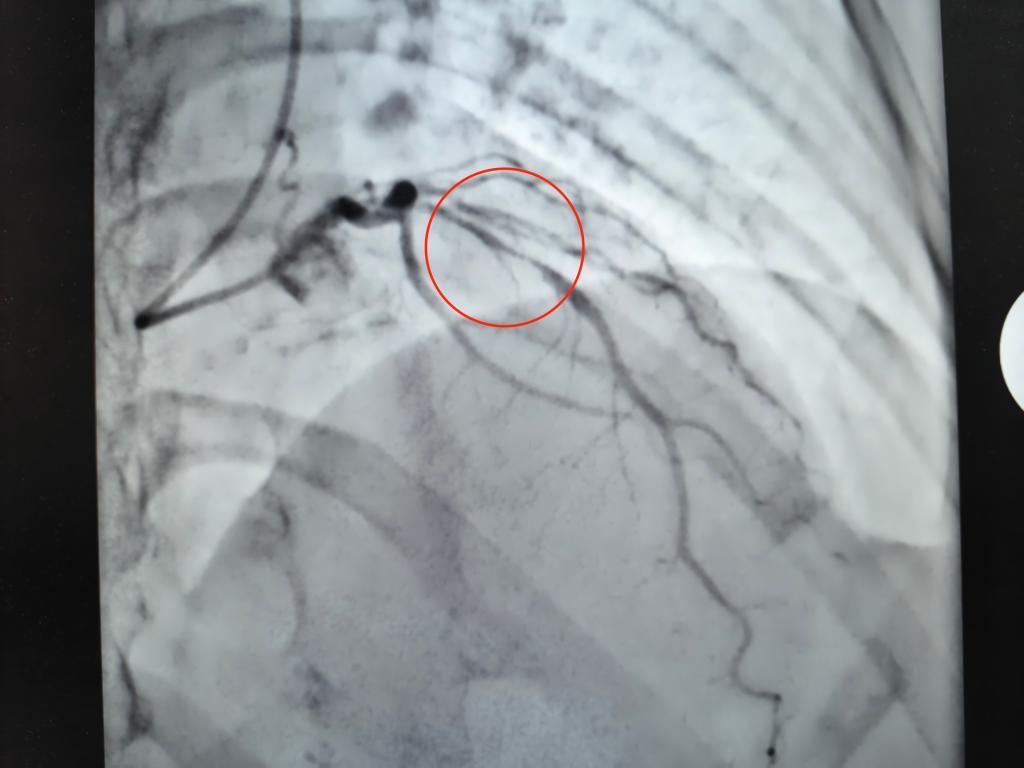

2026年3月20日,在我院心脏介入团队杨凤鸣副主任、曹程浩副主任医师的精心操作下,患者的冠脉药物球囊扩张术顺利完成。术后进行的造影结果显示,原本前降支血管95%的狭窄成功解除,血流恢复通畅状态。目前,患者的生命体征平稳,为她在近期内安全地进行卵巢肿瘤手术奠定了坚实的基础。